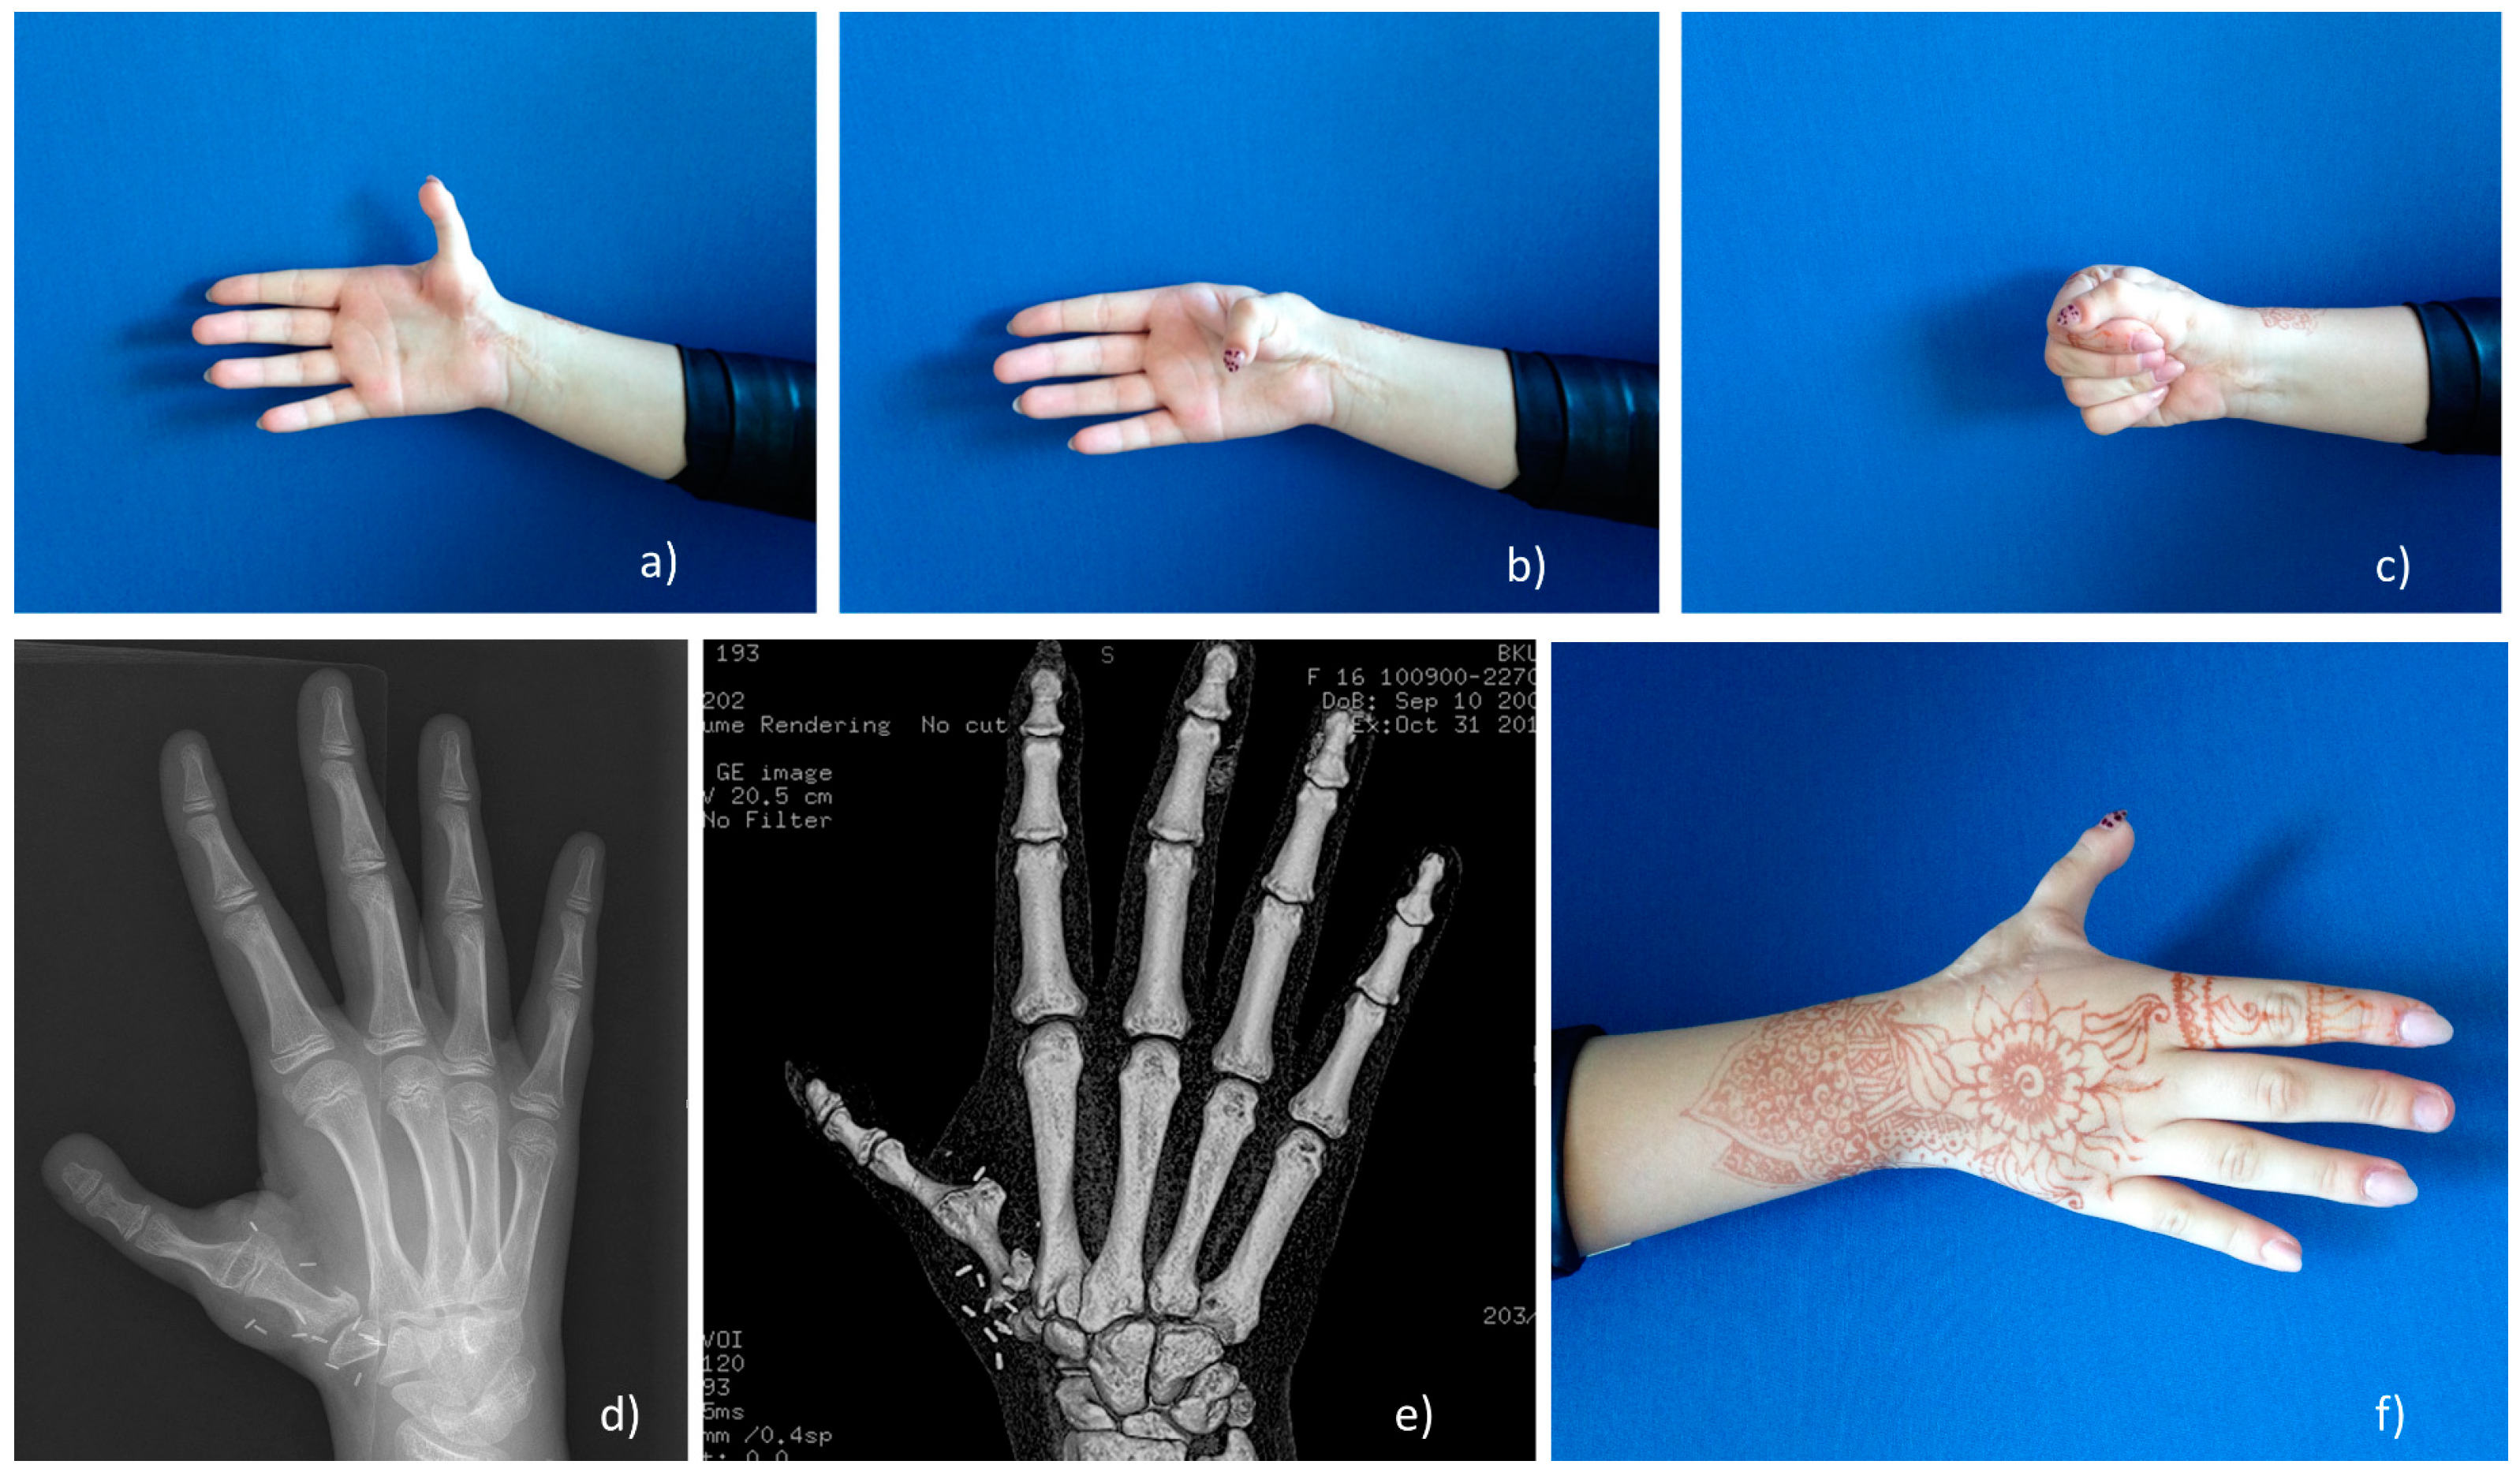

Figure 2. Extensor indicis proprius (EIP) transfer with subperiosteal fixation. (a) Grade II hypoplasia patient with instability of the metacarpophalangeal MCP joint; (b,c) EIP tendon transfer through three incisions; (d,e) subperiosteal fixation of transferred tendon and stabilization test; (f) final fixation with K-wires.

Tendon transfer with subperiosteal fixation was developed in the MC and used since 2007 for the reconstruction of hypoplasia grade II–IIIa. The EIP tendon localizes on the ulnar side of the extensor digitorum (ED) tendon and is separated through three small incisions: first at the second MCP level, second at the wrist level, and third in an S-shape at the level of the first MCP. The EIP tendon is visualized, detached at the level of second MCP joint, and transposed to the thumb. Then, the tendon is pulled through the periosteum and the MCP joint capsule, starting from ulnar side to the radial side supporting and strengthening the ligaments. The distal end can be attached to the EPL tendon at the IP joint level. Fixation is completed by non-absorbable suture 3/0 or 4/0, and then thumb stability can be checked by carefully pulling the MCP joint laterally. After a successful test, the MCP joint is secured with two K-wires. Cast and wires are removed after five weeks, and then hand therapy has to be started in order to improve the motion of the thumb (Figure 2).